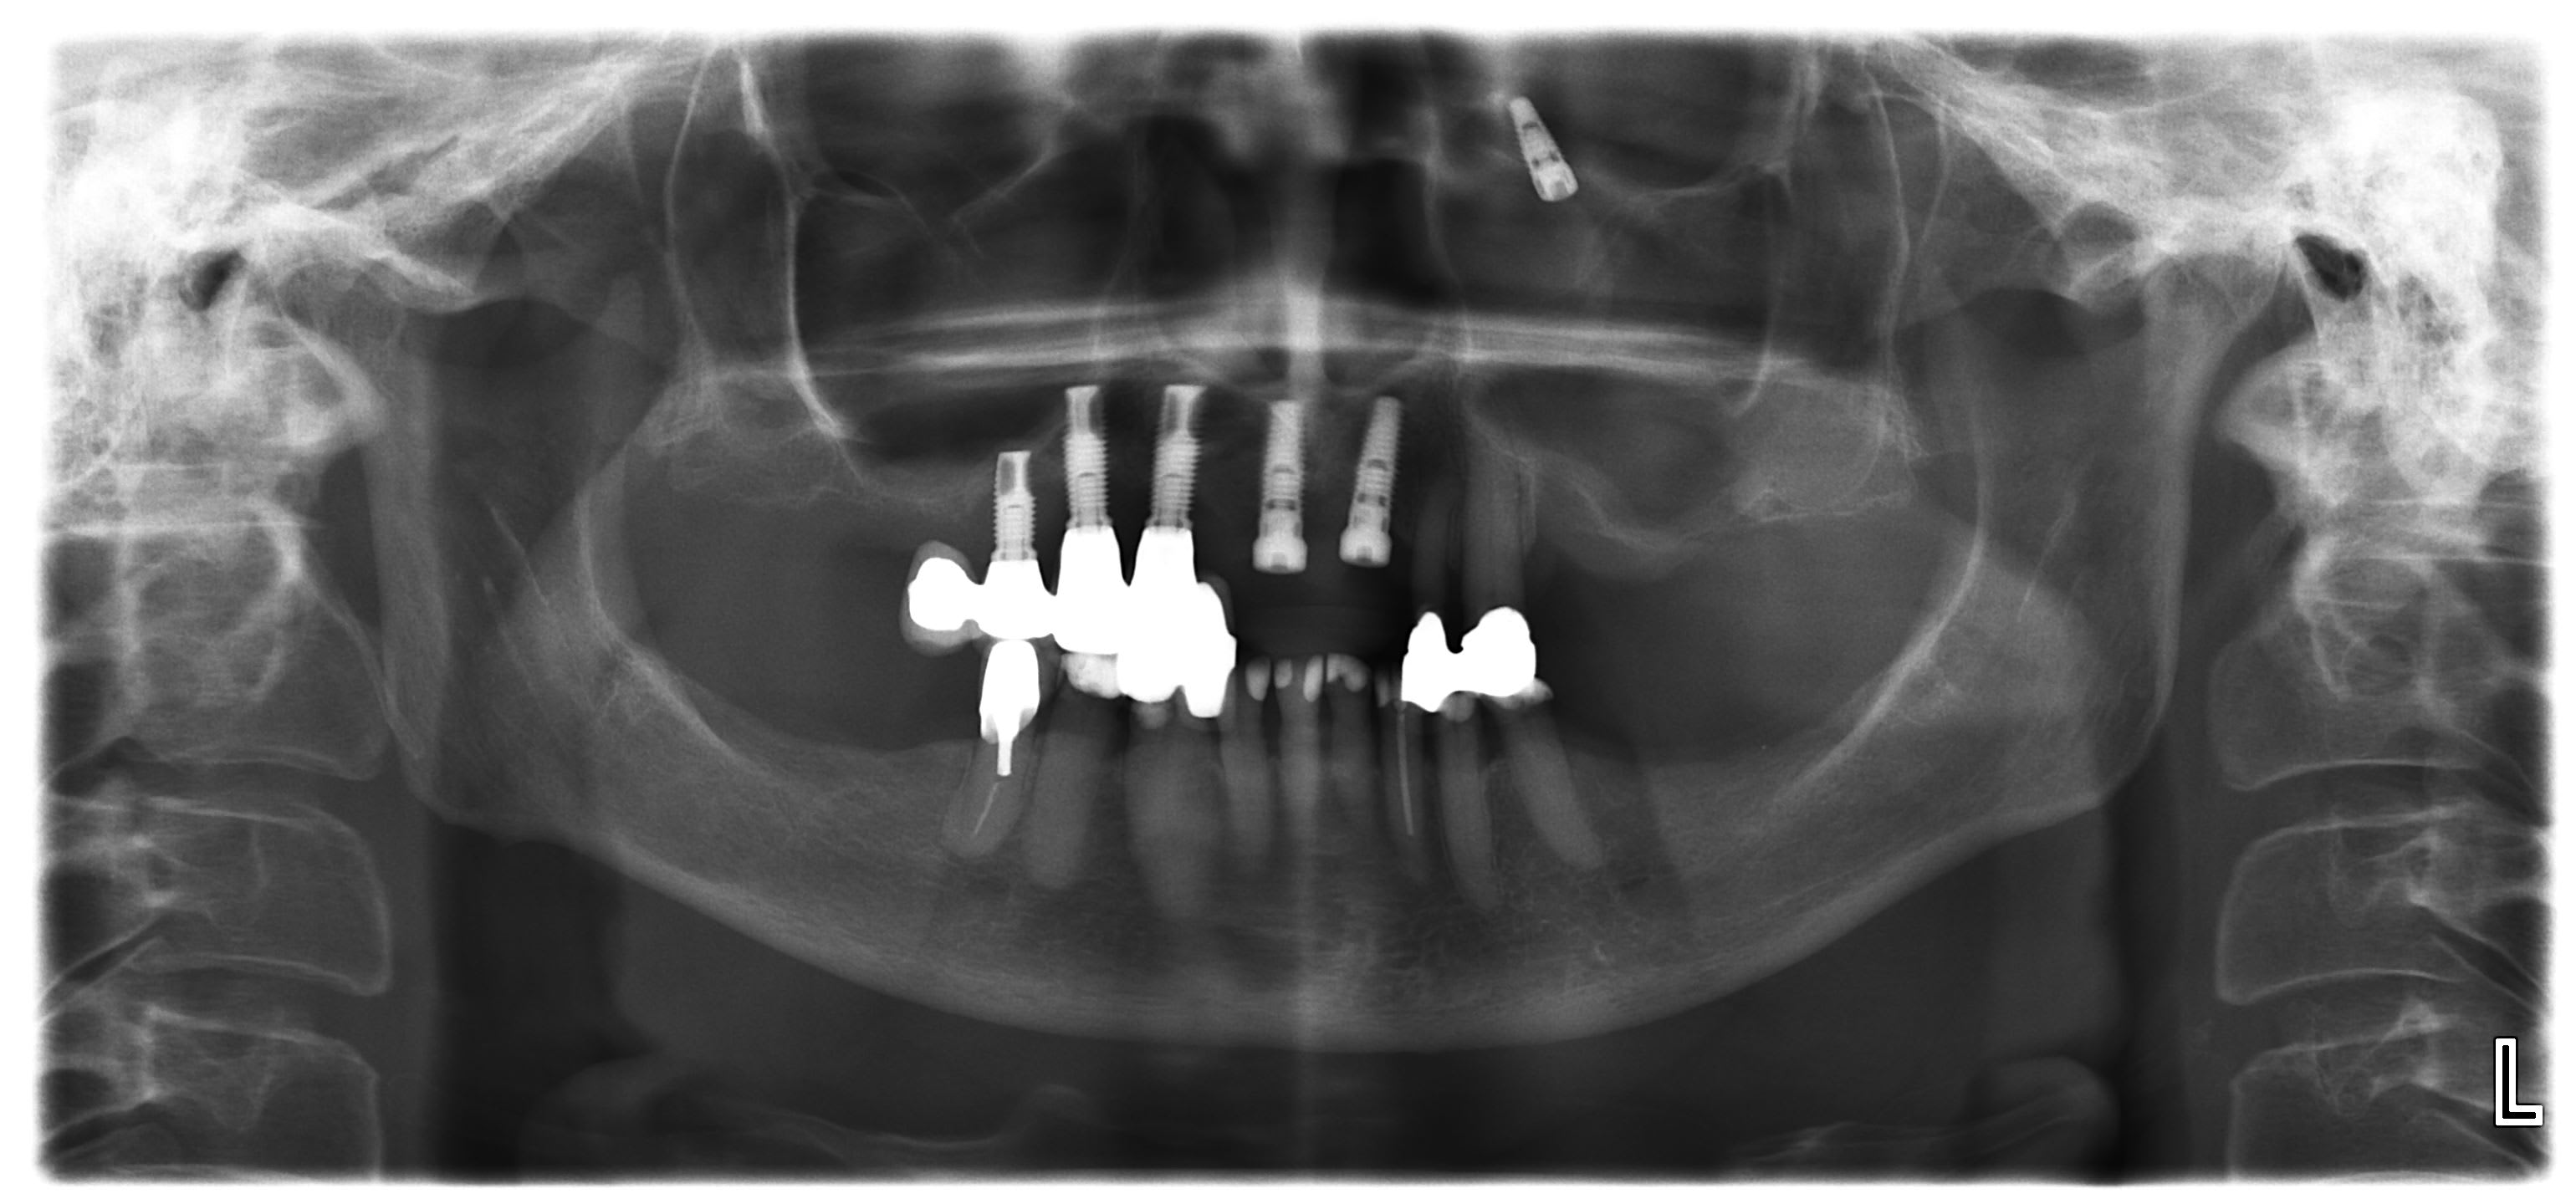

Juste pour info le CBCT qui demontre bien qu une PANO est une somme de projection, rotation etc...

Sur la coupe frontale on voit que la dent est au niveau du cornet inferieur de la paroi nasale et non derriere la cavite orbitaire :0)